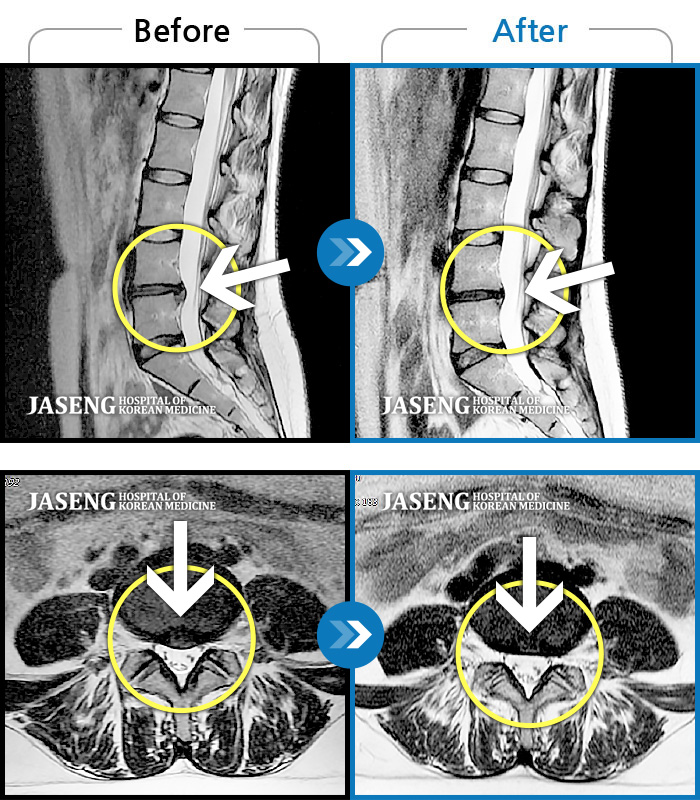

Before

After

환자에게 사전 동의를 받아 동일 조건에서 촬영되었습니다.

개인에 따라 치료 후 부작용이 발생할 수 있으니 의료진과 상담 후 치료를 진행하시기 바랍니다.

좌측 하요추부 통증과 좌측 하지 후면 통증과 저림